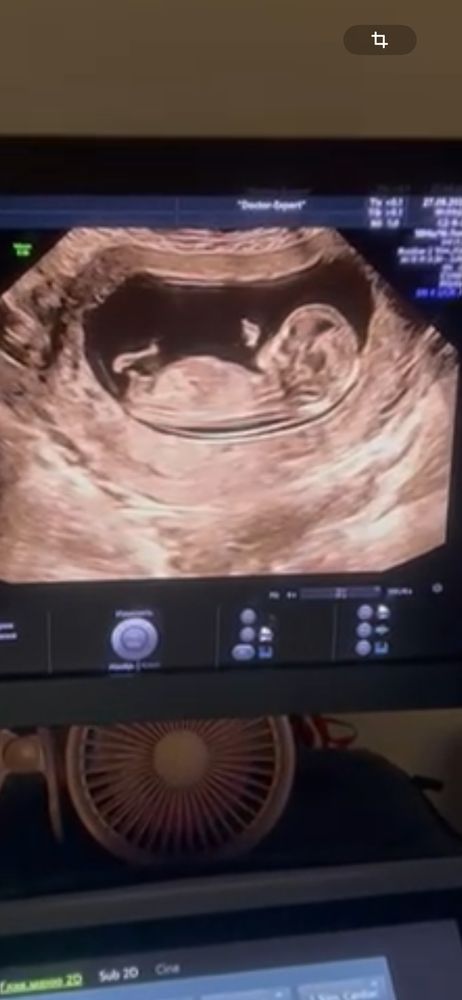

УЗИПредположительно по узи в 12 недель и 2 дня мальчик,может быть девочка?у кого так было?

Best mammy , тут классический угол , бугорок торчит вверх, даже сомнений нет, что это мальчик

С 95% вероятностью мальчик. Малыш у вас хорошо лег, угол классический, у него бугорок торчит вверх, это мальчик скорее всего.